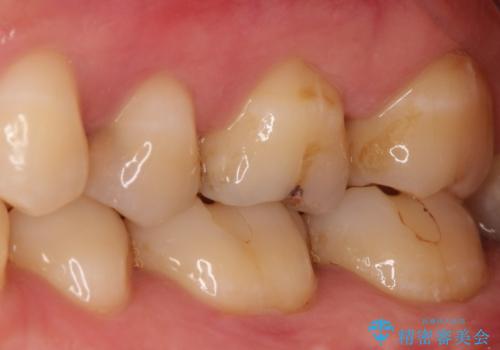

- 奥歯がズキズキ痛いことを主訴に来院されました。

治療にて歯髄は保存できないと判断したため、根管治療を行いセラミッククラウンにて修復しております。